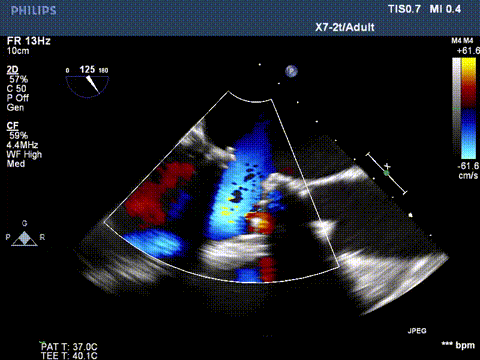

切割前彩超

第一次切割后,导丝紧,血流分为两束

第一次切割后,导丝松,血流又合为一束,但方向改变

第二次切割后,导丝紧,血流分为两束

第二次切割后,导丝松,血流已打散

40w的电凝进行切割,2-3次,每次不超过10秒。

切割时拉紧导丝两端,不切割时,放松导丝,解除对瓣叶的压力后,用彩超观察血流方向,切割成功后,可以观察到彩超血流的改变。